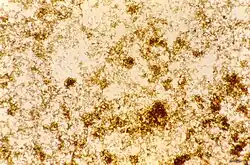

Black-brown pigment was observed by Johann Heinrich Meckel[1] in 1847, in the blood and spleen of a person suffering from insanity.[2] However, it was not until 1849 that the presence of this pigment was connected to infection with malaria.[3] Initially, it was thought that this pigment was produced by the body in response to infection, but Charles Louis Alphonse Laveran realized in 1880 that "malaria pigment" is, instead, produced by the parasites, as they multiplied within the red blood cell.[4] The link between pigment and malaria parasites was used by Ronald Ross to identify the stages in the Plasmodium life cycle that occur within the mosquito, since, although these forms of the parasite are different in appearance to the blood stages, they still contain traces of pigment.

Later, in 1891, T. Carbone and W.H. Brown (1911) published papers linking the hemoglobin degradation with pigment production, describing the malaria pigment as a form of hematin and disproving the widely held idea that it is related to melanin. Brown observed that all melanins were bleaching rapidly with potassium permanganate, while with this reagent malarial pigment manifests not the slightest sign of a true bleach reaction.[5][6] The name "hemozoin" was proposed by Louis Westenra Sambon.[7] In the 1930s several authors identified hemozoin as a pure crystalline form of α-hematin and showed that the substance did not contain proteins within the crystals,[4] but no explanation for the solubility differences between malaria pigment and α-hematin crystals was given.